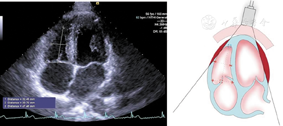

(1)心尖四腔心切面(图7图8图9图10图11图12图13图14图15图16图17图18图19)

心尖四腔切面,在收缩末期测量右心房长径、中份部横径。在右心房中份水平测量横径,在三尖瓣瓣环连线中点向心房底部连线,与横径连线垂直测量长径,避开上腔静脉口